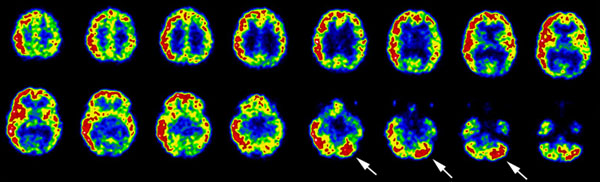

seen at any age.

o

Patients with Hashimoto's thyroiditis develop

other autoimmune disorders with higher frequency and are at increased risk for

developing B-cell lymphoma of the thyroid.

Initially, the gland enlarges